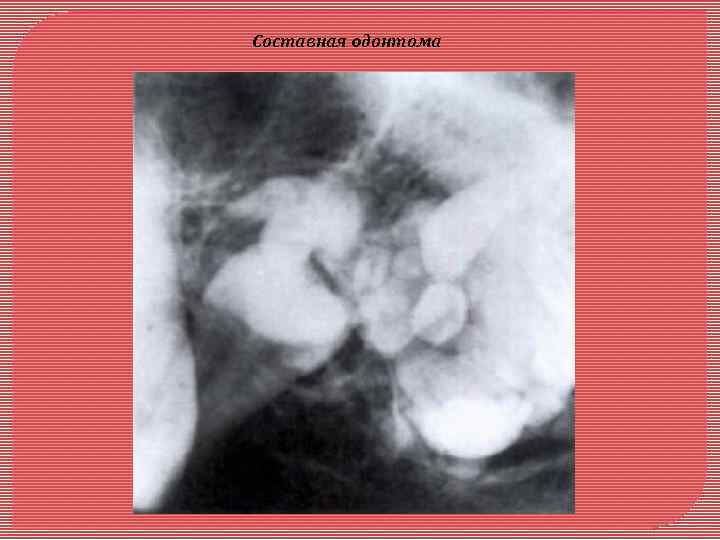

Одонтома - возникает в связи с нарушением развития в период формирования зачатков зубов. Локализация: чаще в верхней челюсти в области премоляров. Растет медленно. Макроскопически имеет капсулу, при больших размерах вызывает деформацию челюсти. Микроскопически различают простые и сложные одонтомы. Сложные одонтомы делят на смешанные (комплексные) и составные Простая одонтома представлена твердыми тканями одного зуба, соединенными а виде нароста в области корня или шейки сущест вующего зуба, «впаянного» в цемент. Может быть представлена зубом с незначительным нарушением топографии его твердых тканей. Сложные одонтомы развиваются из нескольких зубных зачатков. Смешанная (комплексная) одонтома представляет собой хаотичное по топографии сочетание твердых зубных тканей: эмали, дентина, цемента Составная это конгломерат спаянных друг с другом нескольких мелких рудиментарных зубов, в которых топография твердых тканей упорядочена, как в обычных зубах. Рентгенологическая диагностика одонтом не представляет особых трудностей. На фоне обычной костной ткани выявляется очень плотное, округлой формы образование, окруженное ободком просветления (за счет фиброзной капсулы). В зубном ряду, как правило, отсутствует один или несколько зубов.

Составная oдонтома